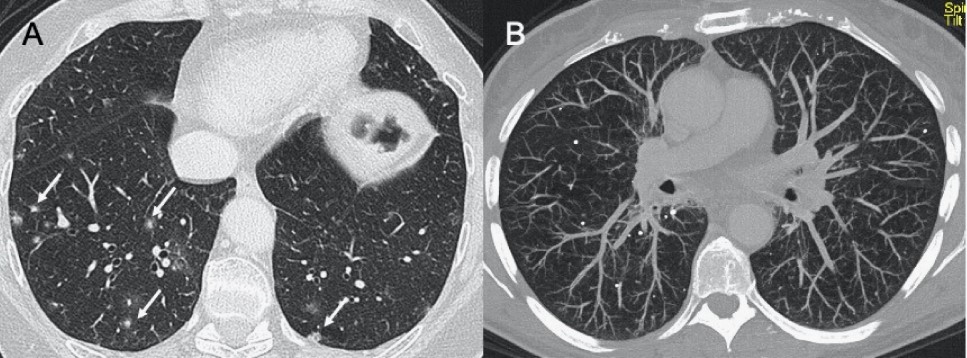

● CXR:肺胸膜下實(shí)變、磨玻璃影、結(jié)節(jié)和網(wǎng)狀結(jié)節(jié)陰影,表現(xiàn)為間質(zhì)性肺炎伴彌漫性肺泡損傷(圖1)。

● CT:早期主要為外周、雙側(cè)磨玻璃影(ground-glass opacities,GGO),伴實(shí)變、小葉間隔和小葉內(nèi)間隔增厚,形成“鋪路石征”模式。空氣支氣管征、血管擴(kuò)大、暈輪征和反暈征也有報(bào)告(圖2)。

圖1 新冠肺炎(COVID-19)的CXR。3例仰臥位CXR顯示胸膜下實(shí)變(箭頭),圖(A,B)顯示雙側(cè)受累,(C)主要為右肺受累

圖2 COVID-19的HRCT。急性期,雙肺(A)彌漫性GGO,小葉周圍型(B)。圖(C,D)顯示2例亞急性間質(zhì)性肺炎,GGO減少,存在胸膜下局灶性實(shí)變和小葉間/小葉內(nèi)間質(zhì)增厚。